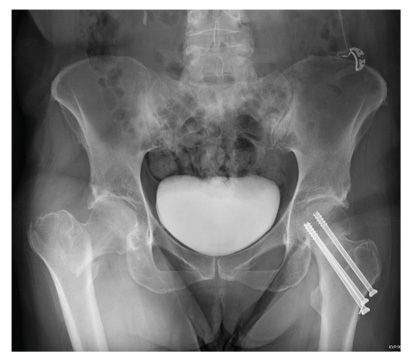

The radiograph demonstrates evidence of contrast material within the bladder. There is evidence of fixation of an old subcapital femoral neck fracture on the left.

There is an acute, mildly displaced right intertrochanteric fracture of the right hip. The orthopedic service was consulted, and plans were established to subsequently fix this fracture surgically.